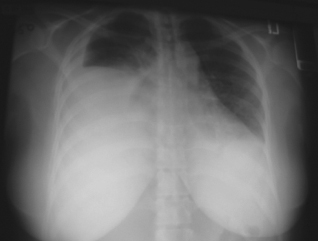

Vital signs and oxygen saturation were normal. The patient had decreased breath sounds with dullness to percussion bilaterally. The chorionic gonadotropin level was 295 mIU/mL. Results of a complete blood cell count, chemistry panel, coagulation studies, arterial blood gas analysis, and urinalysis were within normal limits. A chest x-ray film revealed bilateral pleural effusions, greater on the right.

A right thoracentesis was performed, and 1500 mL of clear yellow pleural fluid was aspirated. Analysis showed that the effusion was transudative. Fluid culture was negative for pathogens, and cytology results were normal. Over the next 6 days, the serum progesterone level increased from 65 to 222 ng/mL and the chorionic gonadotropin level rose to 3334 mIU/mL. A 2-dimensional echocardiogram was normal.